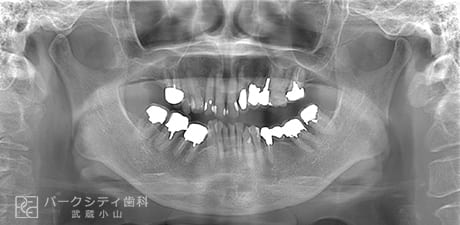

CASE.01

- 主訴

- 全体的に綺麗にしたい

- 治療法

- 矯正歯科治療

インプラント治療

セラミック治療

- 治療期間

- 2年

- 費用

- トータル¥5,000,000程度